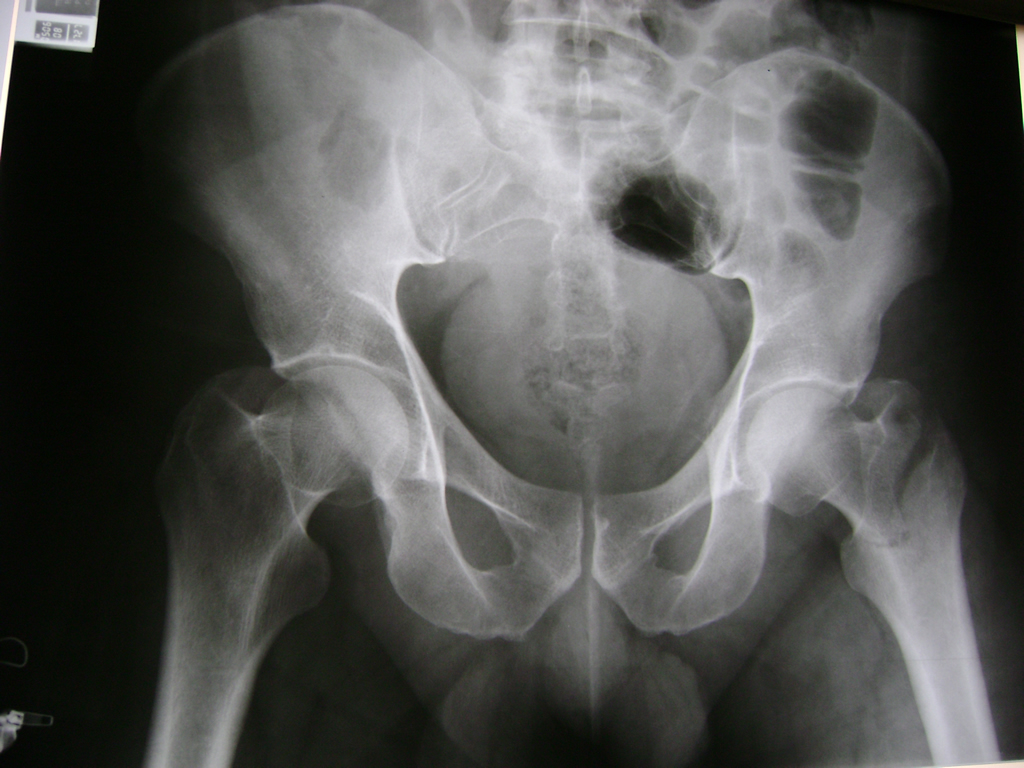

La cirugía de fractura de cadera se realiza para reparar una ruptura en la parte superior del hueso del muslo. Este hueso se denomina fémur.

Es parte de la articulación coxofemoral. Si una fractura de cadera no recibe tratamiento, es posible que deba permanecer en una silla o en la cama.

Esto puede llevar a otros problemas de salud potencialmente mortales, sobre todo si usted es una persona mayor.